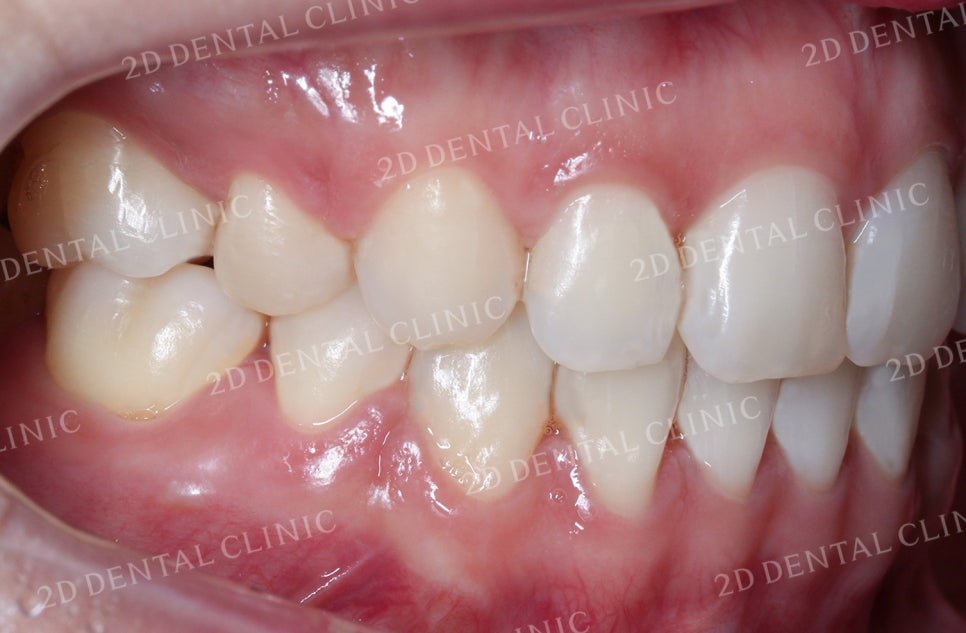

좌우의 안모 사진입니다.

표시된 부분에서 완전히 맞물리지 못한

치아 사이의 틈이 발견되고 있네요.

이러한 교합면 사이의 빈 공간은

음식물 섭취 시 불편을 유발하는 원인 중 하나입니다.

좌측의 안모 사진입니다.

치열의 총생으로 인해

송곳니 부근에 생겼던 틈들이

잘 덮혀진 모습입니다.

우측 역시 비어있던 공간이

상악의 교정치료 후